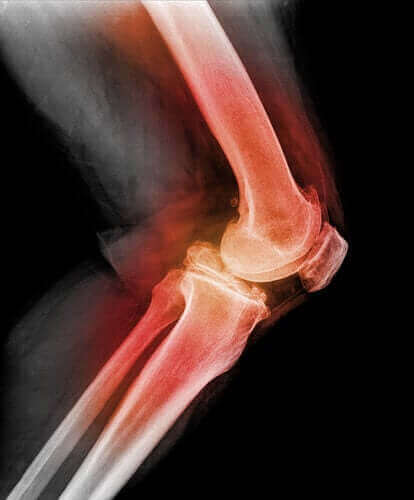

За да диагностицираме пателарна или дислокация на капачките на колената, лекарят ще докосне пателата и свива коляното, движейки го в различни посоки. С използването на рентгенови лъчи, магнитен резонанс (MRI), или компютърна томография (CT), той може да види изображения на разместената ключица на коляното и други наранявания на коляното.